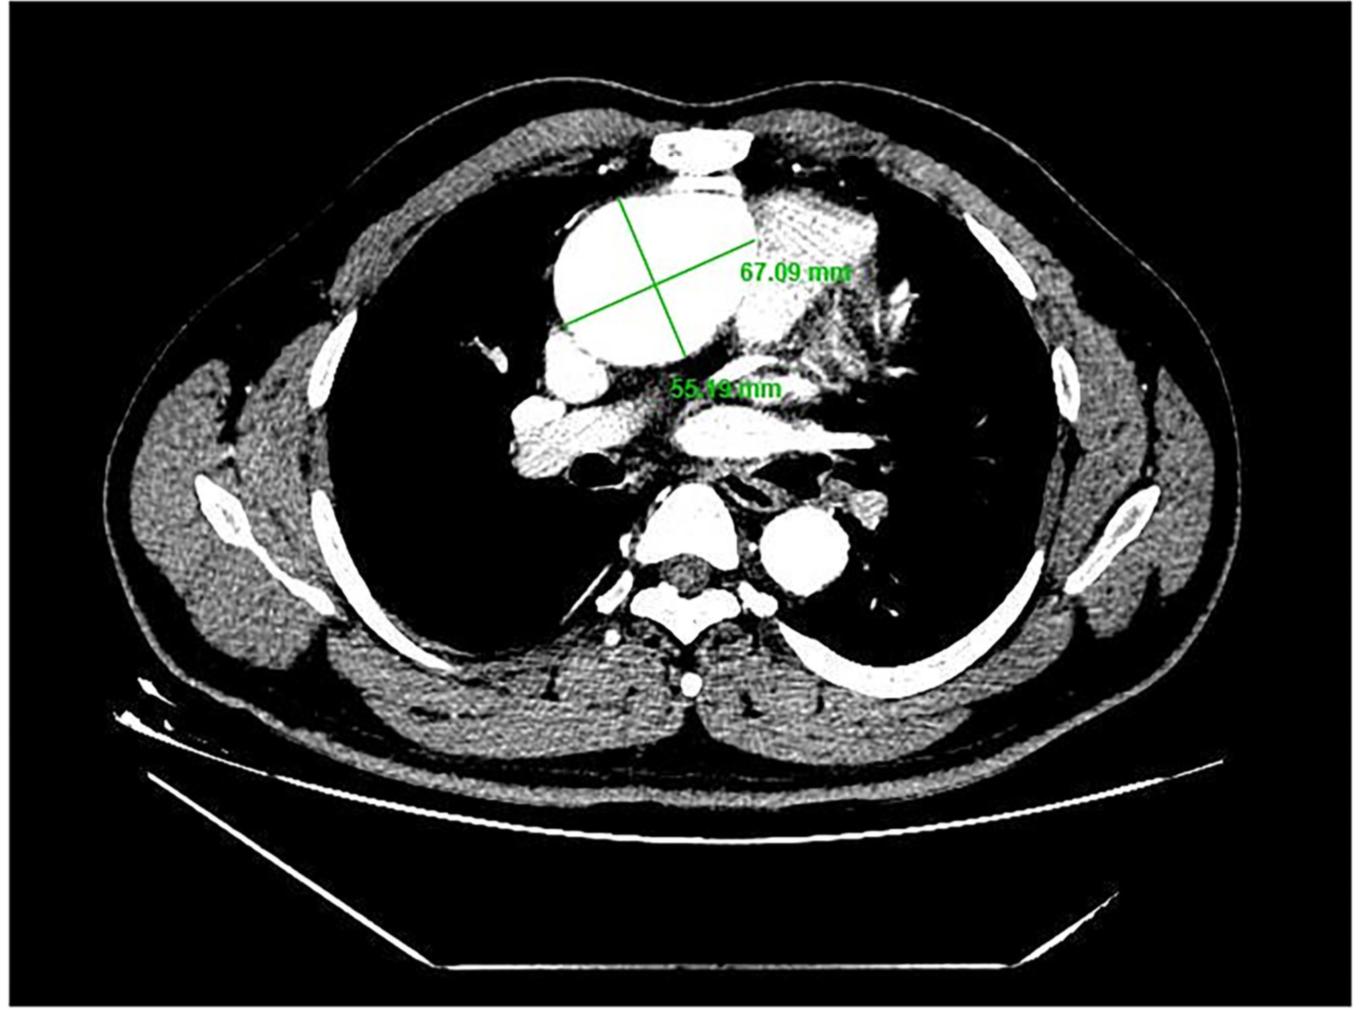

一名39岁男性患者因持续咯血3周而入院。患者是典型的TOF,而不是SD I型TOF。此前,他接受了法洛四联症根治性手术,包括缓解右心室流出道梗阻,并在21岁时修复室间隔缺损。在胸骨左侧第二肋间间隙发现舒张期杂音,其他体检结果均为阴性。根据心脏超声心动图观察到的结果,诊断为窦管连接部和升主动脉扩张(环,3.17厘米;窦,最大5.82厘米;近端升主动脉,4.14厘米)和主动脉瓣关闭不全合并严重AR(图1A)。术前胸部CT扫描显示主动脉根部直径为55.19 mm×67.09 mm(图2)。同时,还检测到LVOT的局部阻塞(图1B),LVOT阻塞的梯度为23 mmHg。经临床评估,该患者接受了包括David I plus修复主动脉瓣手术和同时重建左心室流出道的手术。

图2.主动脉根部直径为55.19mm×67.09mm